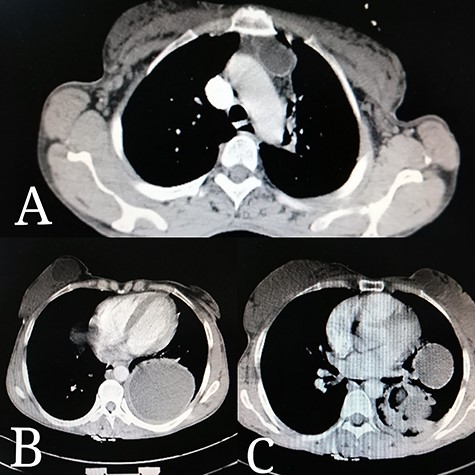

Abdominal ultrasound delineated multiple cystic lesions in the liver and the spleen. Computed tomography (CT) scan showed up to six rounded homogenous low-density cysts in both lobes of the liver, ranged from 0.15 to 0.17 m, and one large cyst in the spleen, containing multiple peripheral small vesicular cysts (Fig. 1). CT scan showed a 0.03 × 0.07 m cyst in the upper mediastinum, adjacent to the aortic arch (Fig. 2A); two rounded well-defined homogenous cysts in the lower lobe of the left lung, measured 0.17 × 0.17 m, and in both breasts (Fig. 2B and C) and a single large 0.2 × 0.13 m oval homogenous cyst above the right gluteal muscles (Fig. 3).

Thoracic CT scan reveals: (A) a 0.03 × 0.07 m cyst in the upper mediastinum, adjacent to the aortic arch. (B) A rounded cyst in the right breast. (C) Few rounded cysts in the left breast. (B, C) Two rounded homogenous cysts in the lower lobe of the left lung, measuring 0.17 × 0.17 m.